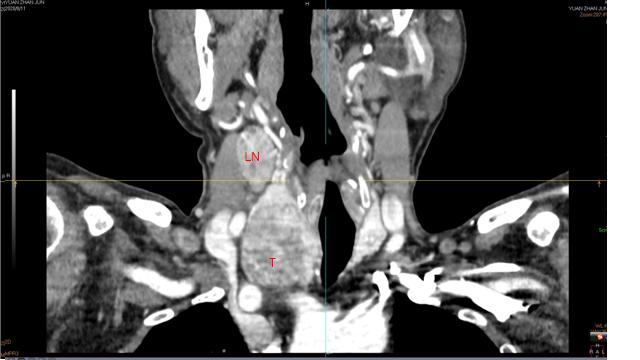

二、下一步?评估病变范围

- 电子计算机断层成像(CT)

专科检查:气管居中,双侧颈动脉搏动正常,颈静脉无怒张,肝颈静脉回流征阴性。右侧甲状腺区可触及肿物,大小约4*4cm,质中,表面光滑,无压痛,随吞咽活动,表面皮肤正常,肿物与皮肤无粘连。左侧甲状腺区及峡部未触及明显肿物。右颈部Ⅲ、Ⅳ区可触及肿大淋巴结,较大者大小约3*2cm,质中,表面光滑,无压痛,活动。左侧颈部未触及异常肿大淋巴结。